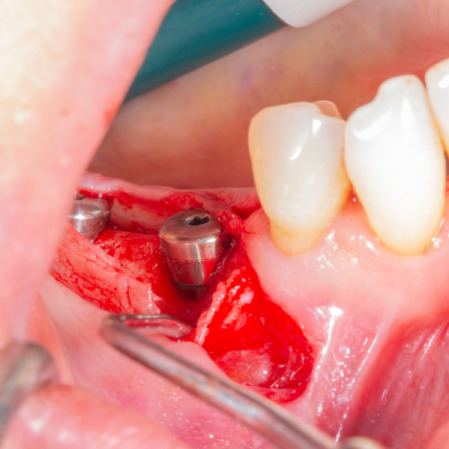

Diş çekiminin yıllar önce yapılmış olmasına bağlı olarak ince kemik varlığında implant ve kemik grefti uygulandı